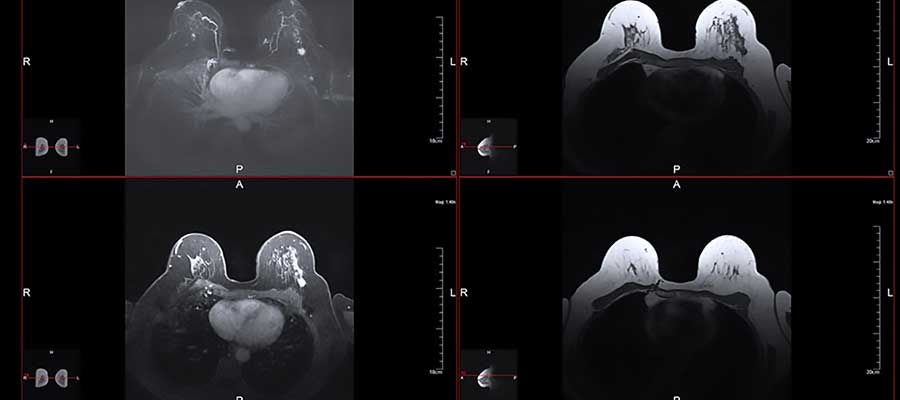

MRIs are important pieces of equipment in healthcare. They allow for the accurate capture of organs and areas of the body which makes diagnosing diseases a lot easier. So far, they’re the most accurate machines that can be used to capture images of soft tissues in the body. Soft tissues include almost everything that isn’t made of bone.